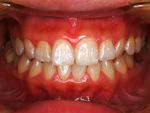

◆歯周病治療

25歳以上の日本人の80%が歯周病であるというデータが出ています。

歯周病とは「ハグキが炎症を起こし赤く腫れたり出血したりする歯肉炎」と「歯肉炎が進行して歯槽骨などの歯周組織が破壊される歯周炎」の総称です。自覚することなく進行する病気(サイレントディジーズ)です。歯の喪失のほとんどの原因が歯周病といっても過言ではありません。

歯周治療の流れは、症例により病態はさまざまです。まず歯周検査・X線診査を行い歯肉と歯槽骨の状態を把握します。プラークコントロールと除石(歯肉縁上・歯肉縁下)が中心となりますが、部位によっては歯周外科手術が必要となる場合もあります。

~術前~

歯周治療写真

~術後~